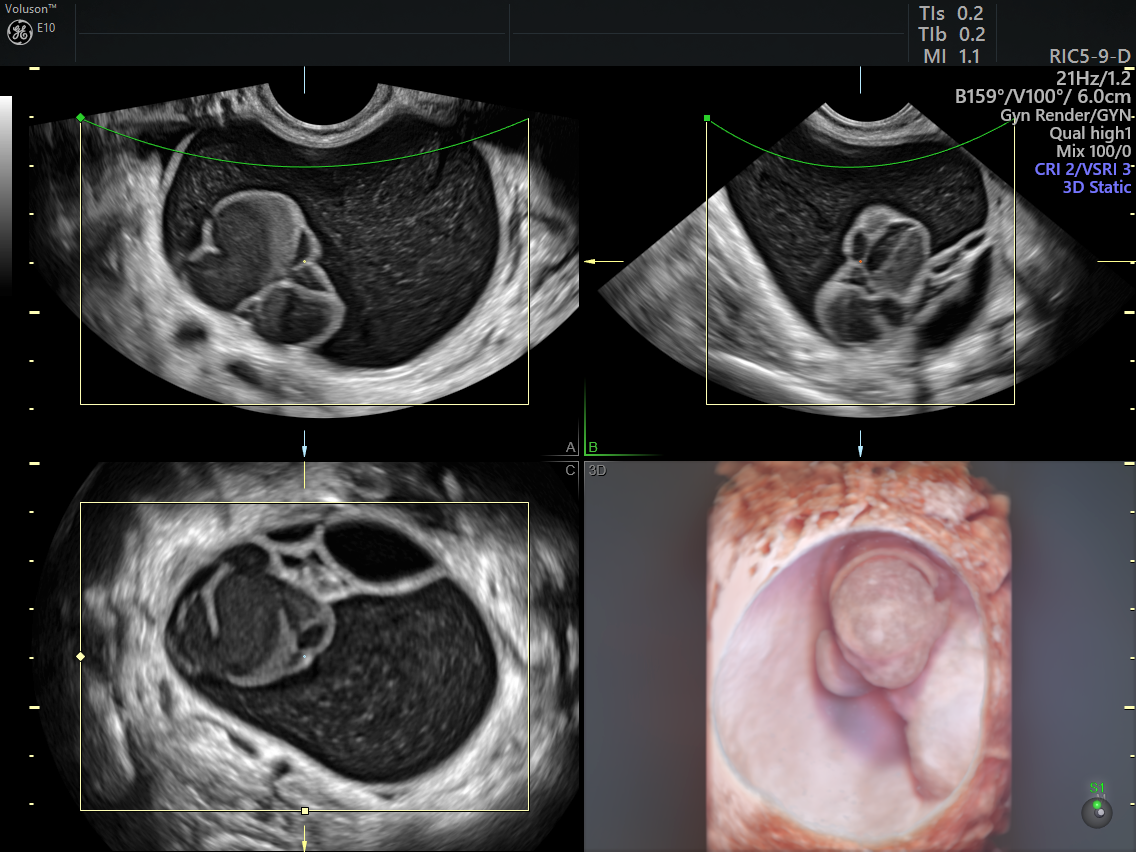

from www.volusonclub.net